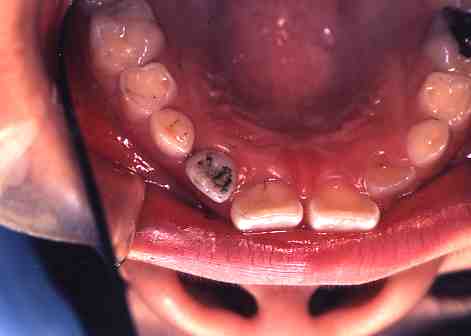

1.術前(ミラー像)

歯の舌面(裏側)が

へこんでいて虫歯に

なりやすい状態です。